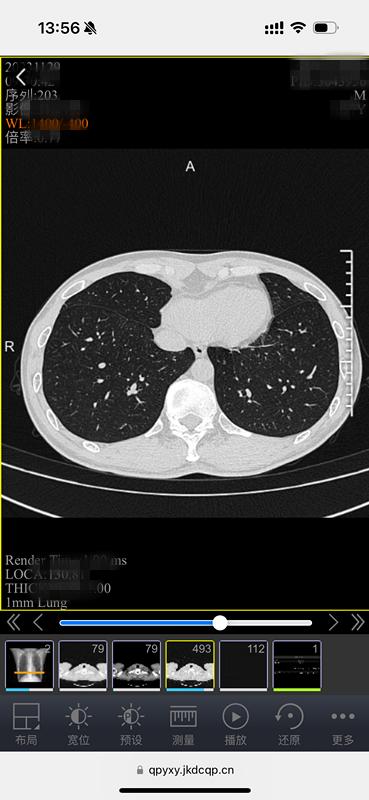

原来,这是中山医院青浦分院为方便百姓就医、优化就诊流程,推出的又一项便民措施——“电子胶片”智慧医疗服务。放射科主任武刚介绍,所谓“电子胶片”,就是患者在中山医院青浦分院做了放射DR、CT、磁共振等检查后,无需再去窗口等待打印传统胶片,用手机、ipad等移动终端扫描报告单上的二维码,检查的影像资料就可以全部在手机上显示,临床医生也可以使用电脑查看影像资料。

电子胶片,不光保存方便,携带方便,医生还能看原始数据。什么叫原始数据?简单地说就是“电子胶片”包含全部图像,支持对图像进行放大缩小、调节明暗等专业操作,能更好地看清病灶,更利于诊断。